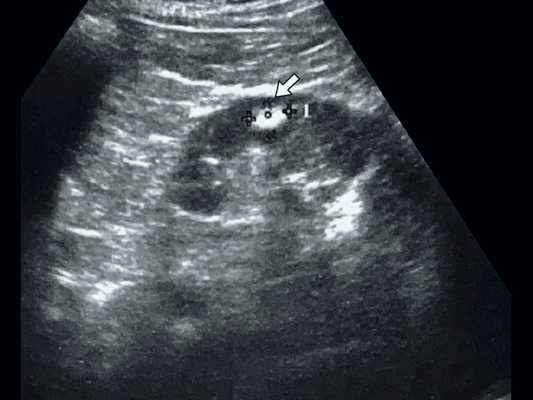

Данные УЗИ: правая почка с четкими неровными контурами, размером 12,5х6,5 см, подвижная при дыхании. Паренхима верхнего сегмента почки толщиной 1,6 см. В нижнем сегменте почки, преимущественно экстраренально определяется округлое образование повышенной эхоструктуры, до 3 см в диаметре. Подвижность почки 2 см.

Левая почка с четкими неровными контурами, размером 11,5х5,5 см. Паренхима однородная, толщиной до 1,7 см. Чашечно-лоханочная система не дилатирована. На границе верхнего и среднего сегментов определяется округлое образование повышенной эхогенности, 1,7 см в диаметре. Подвижность почки - до 2 см (рис. 1).

Рис. 1. Ультрасонограмма - стрелкой указано округлое образование в нижнем сегменте почки.